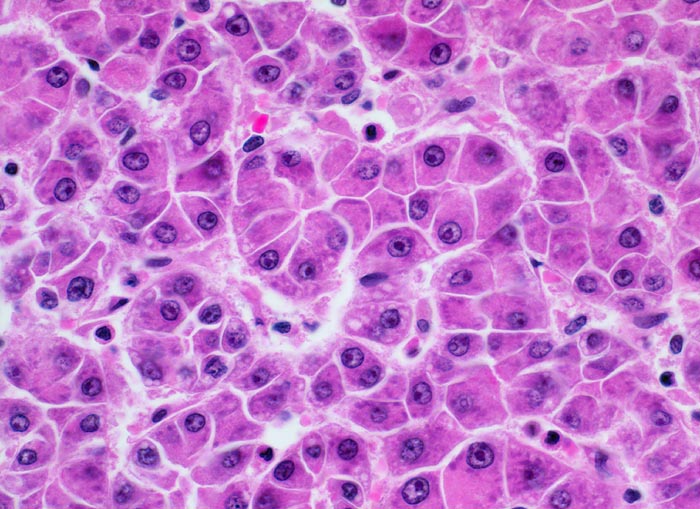

Makroskopisch imponiert das hepatozelluläre Karzinom als solitäre grosse Tumormasse, als zahlreiche zirrhoseartige Knoten oder als scharf begrenzter Knoten mit oder ohne Kapsel. Die tumorfreie Leber ist in der Mehrheit der Fälle zirrhotisch umgebaut. Mikroskopisch bilden die Tumorzellen mehr als 2 Zellen breite Trabekel (> 1237), kompakte Tumormassen (> 1229) oder pseudoglanduläre Strukturen (dilatierte Canaliculi) (> 1212) (> 1199). Desmoplastisches Bindegewebe fehlt meist. Innerhalb des Tumors fehlen Portalfelder. Es finden sich lediglich Arterien. Etwa bei der Hälfte der Karzinome lässt sich intrazytoplasmatische oder intracanaliculäre Galle (> 1238) nachweisen. Immunhistochemisch lassen sich mit einem polyklonalen Antikörper gegen Carcinoembryonales Antigen (CEA) Gallecanaliculi zwischen den Tumorzellen nachweisen. Die Tumorzellen bilden keinen Schleim.

• Die Tumorzellen erinnern an normale Hepatozyten, sind aber kleiner als die Hepatozyten und die Kern-Zytoplasmarelation ist deutlich erhöht. Das Zytoplasma ist basophiler als das der angrenzenden Hepatozyten.

• Galle ist sichtbar in den Pseudodrüsen.

Die Tumorzellen zeigen eine hepatozelluläre Differenzierung (Gallebildung, Ausbildung von Gallecanaliculi).